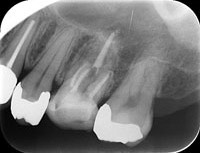

レントゲン

問診・視診・触診・打診・レントゲン検査(単純X線撮影、CT)・歯周ポケット検査などにより、歯を詳しく検査します。病気の原因を診断した上で治療方法を決定します。

レントゲン画像

可能な限り根の細菌を減らした後、根管充填材を根に緊密に充填し、細菌が増殖し得るスペースを無くします。